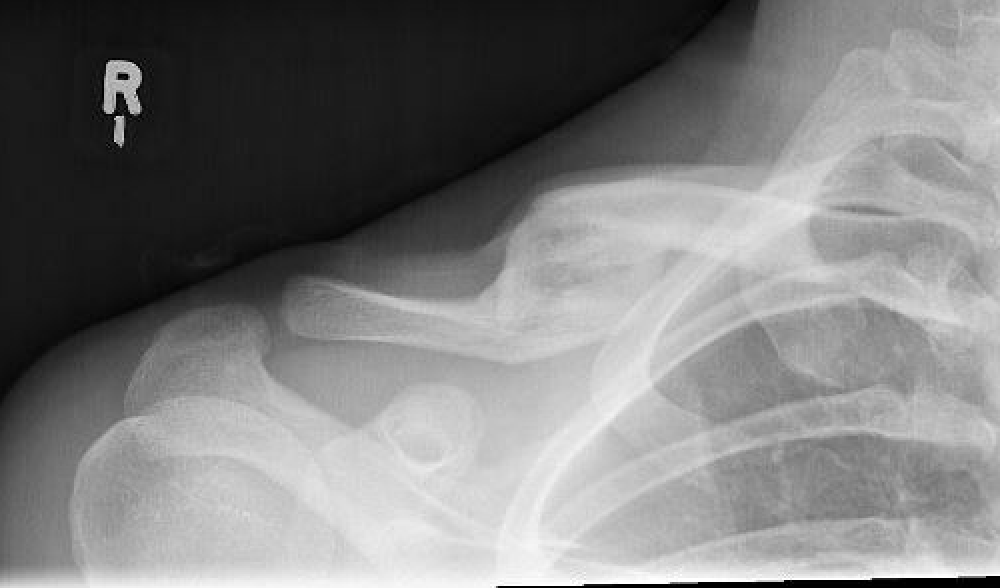

Xray

Shortening

Displacement

- the proximal fragment elevated by sternocleidomastoid

- lateral fragment sags down with weight of shoulder